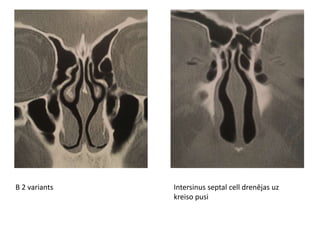

Frontāla dobuma mukocēle

MukocēleVII

MukocēleVII Diagnostika Klīnika + radioloģija+ histoloģija Radioloģija CT • Plānas dobuma sienas; paplašināti dobumi • Kaula erozijas • Dobuma saturs homogēns, gaisu nesaturošs; izskats atkarīgs no hidratācijas pakāpes